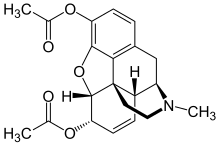

3,6-diesters of morphine

- Acetylpropionylmorphine

- 3,6-Dibutanoylmorphine

- Diacetyldihydromorphine (dihydroheroin, acetylmorphinol)

- Dibutyrylmorphine

- Dibenzoylmorphine (first designer drug)

- Diformylmorphine

- Dipropanoylmorphine

- Heroin (diacetylmorphine)

- Nicomorphine

Structures

| 3,6-diesters of morphine | ||||

|---|---|---|---|---|

Acetylpropionylmorphine Acetylpropionylmorphine |

3,6-Dibutanoylmorphine |  Diacetyldihydromorphine Diacetyldihydromorphine(dihydroheroin, acetylmorphinol) | ||

Dibutyrylmorphine Dibutyrylmorphine |

Dibenzoylmorphine Dibenzoylmorphine |

Diformylmorphine Diformylmorphine | ||

Dipropanoylmorphine Dipropanoylmorphine |

Heroin Heroin(diacetylmorphine) |

Nicomorphine Nicomorphine | ||